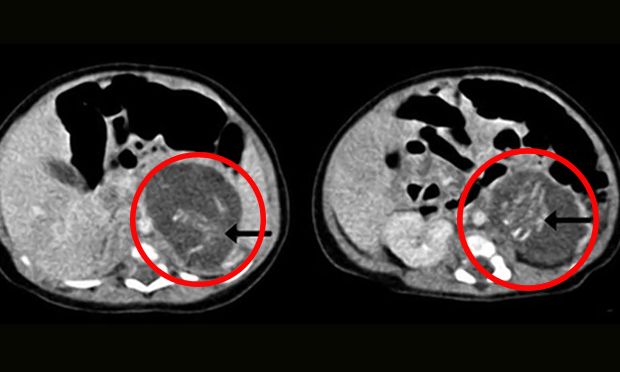

Bild: Hong Kong Medical Journal